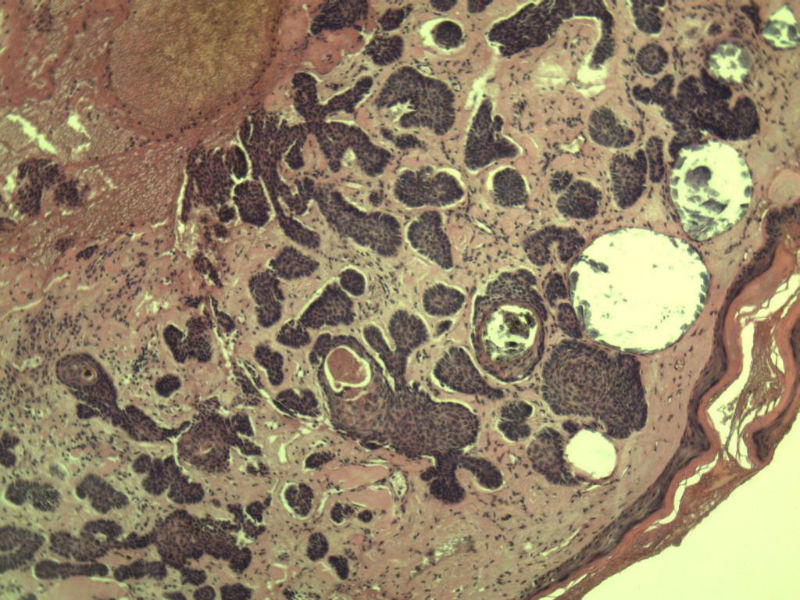

女 67岁 临床考虑面部色素痣 1*0.8 cm  请问各位老师 这是什么? 谢谢!面部包块图1

毛母/发细胞瘤鉴别基底细胞癌,可做CD10,CK7,CK20鉴别

考虑毛发上皮瘤,需除外基底细胞癌。

毛发上皮瘤,需与基底细胞癌鉴别

第一例:毛发上皮瘤

第一例:毛发上皮瘤,与基底细胞瘤区别明显。

第一例  毛发上皮瘤,和基底细胞癌鉴别一下

第一例考虑毛母细胞瘤,第二例考虑基底细胞癌。

毛母细胞瘤

第一例:毛母细胞瘤;第二例:基底细胞癌

第一例,毛发上皮瘤;第二例,基底细胞癌。

一毛发上皮瘤